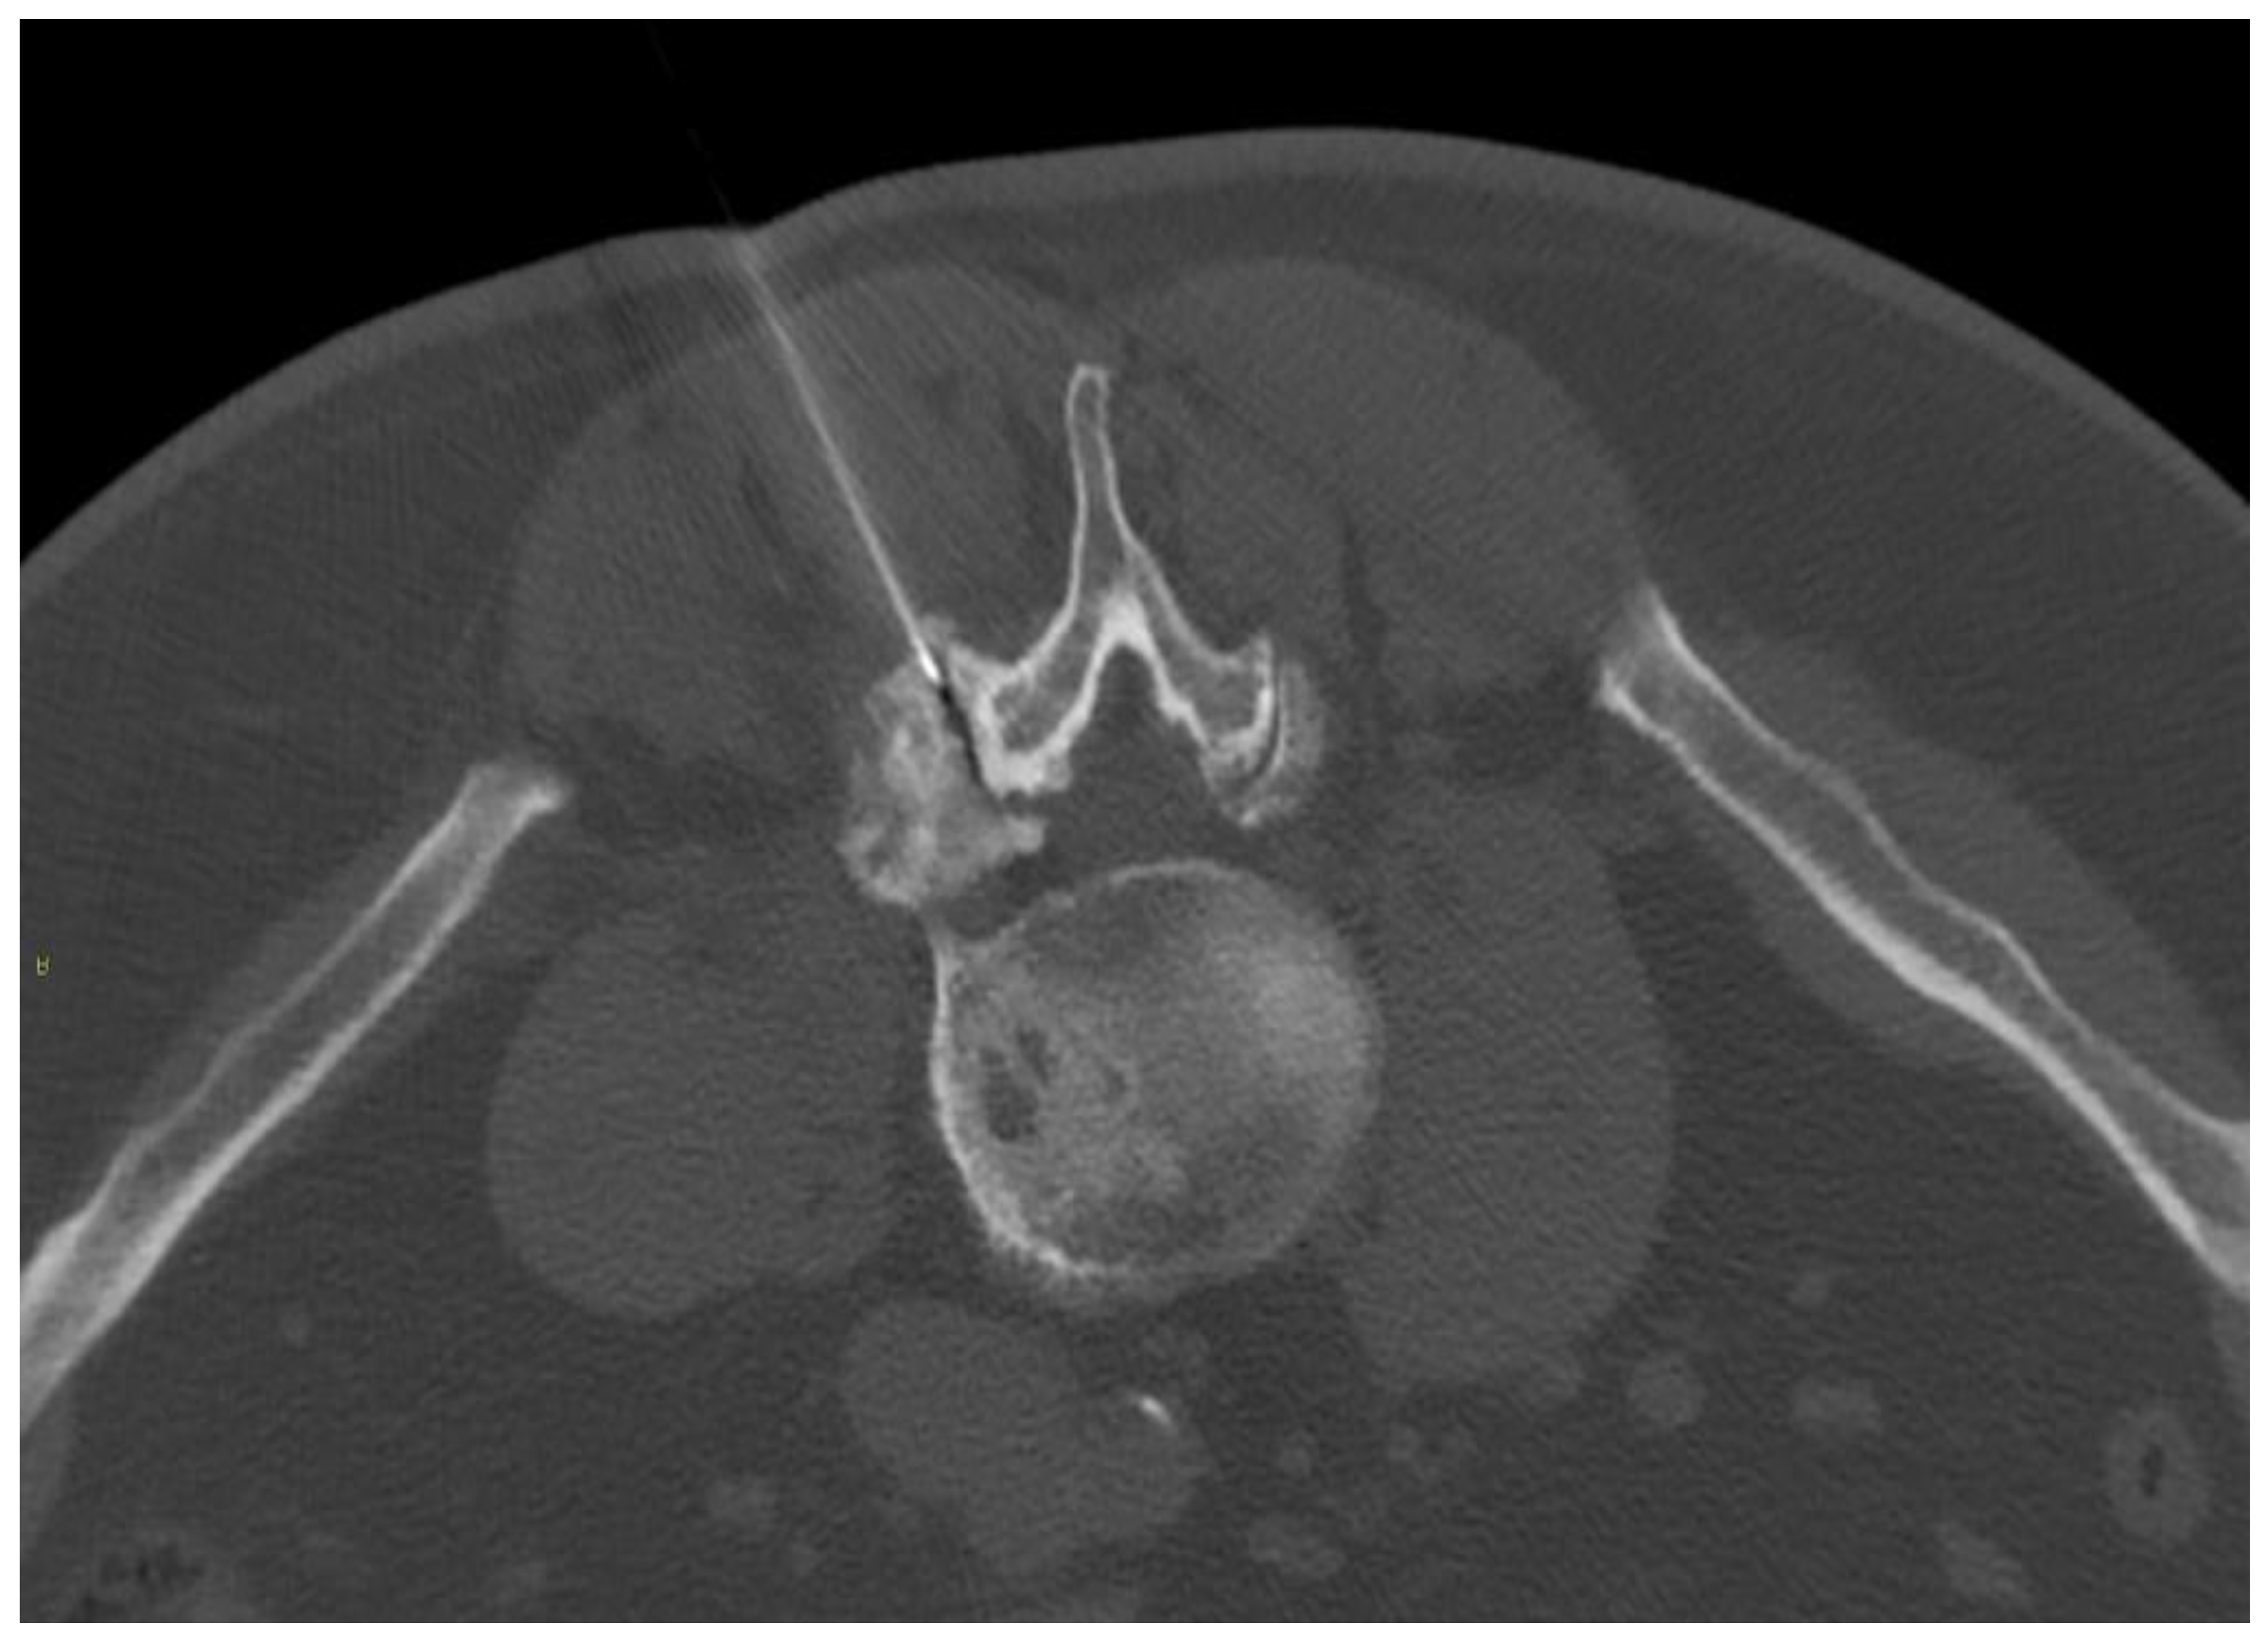

- Napoli, A.; Alfieri, G.; De Maio, A.; Panella, E.; Scipione, R.; Facchini, G.; Albisinni, U.; Spinnato, P.; Nardis, P.G.; Tramutoli, R.; et al. CT-Guided Pulsed Radiofrequency Combined with Steroid Injection for Sciatica from Herniated Disk: A Randomized Trial. Radiology 2023, 307, e221478. [Google Scholar] [CrossRef] [PubMed]